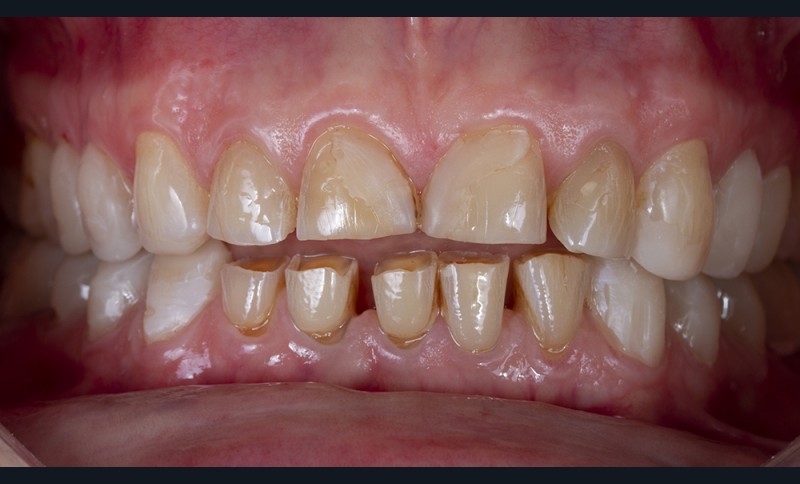

En effet, certaines situations cliniques (perte de dimension verticale et des fonctions masticatoires ou esthétiques) requièrent l’utilisation de matériaux dont la résistance mécanique permet d’envisager une prise en charge globale et pérenne du patient [6]. Ces matériaux (céramiques renforcées ou polymères hybrides) imposent des préparations plus invasives pour répondre aux exigences de résistance mécanique propre à chacun d’eux [7]. Toutefois, afin de minimiser la perte tissulaire, le concept de préparation à travers un mock-up postérieur s’est imposé comme l’option la plus judicieuse [8, 9]. Si la réalisation de ce mock-up peut paraître simple face à une denture naturelle usée de façon homogène, il en est tout autrement lorsque l’usure est irrégulière. Ces situations se rencontrent fréquemment quand le patient est partiellement équipé de restaurations périphériques anciennes ayant engendré des phénomènes d’usure par abrasivité différentielle entre la céramique et l’émail antagoniste.

En outre, l’analyse clinique initiale permet d’appréhender deux situations cliniques très distinctes : la perte de dimension verticale (DVO) ou, au contraire, le maintien de celle-ci par égression compensatrice des dents. De façon très schématique, une usure rapide, de type érosive, entraîne plus facilement une perte de dimension verticale, alors qu’une usure lente permet souvent à l’organisme d’effectuer une égression compensatrice [11].

Enfin, une analyse attentive des courbes d’occlusion est menée, notamment dans les cas d’édentements non compensés ou lorsque des restaurations en céramique sont déjà présentes [12] (fig. 1). En effet, la présence de ces dernières peut entraîner une usure différenciée de la dent naturelle antagoniste.

Ainsi, les usures engendrent, dans la majorité des cas, des perturbations au niveau des courbes d’occlusion, lesquelles devront être corrigées lors de la réalisation du wax-up [13].